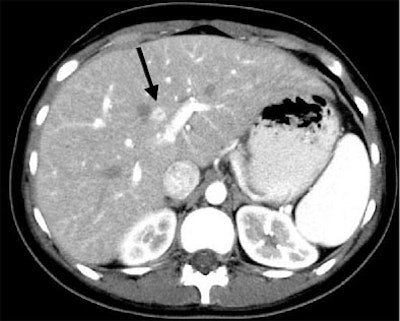

| Another patient with fever after prolonged neutropenia. Above, arterial-phase CT shows a type 2b lesion (arrow). Below, portal-venous phase fails to show a lesion. |

![]() |